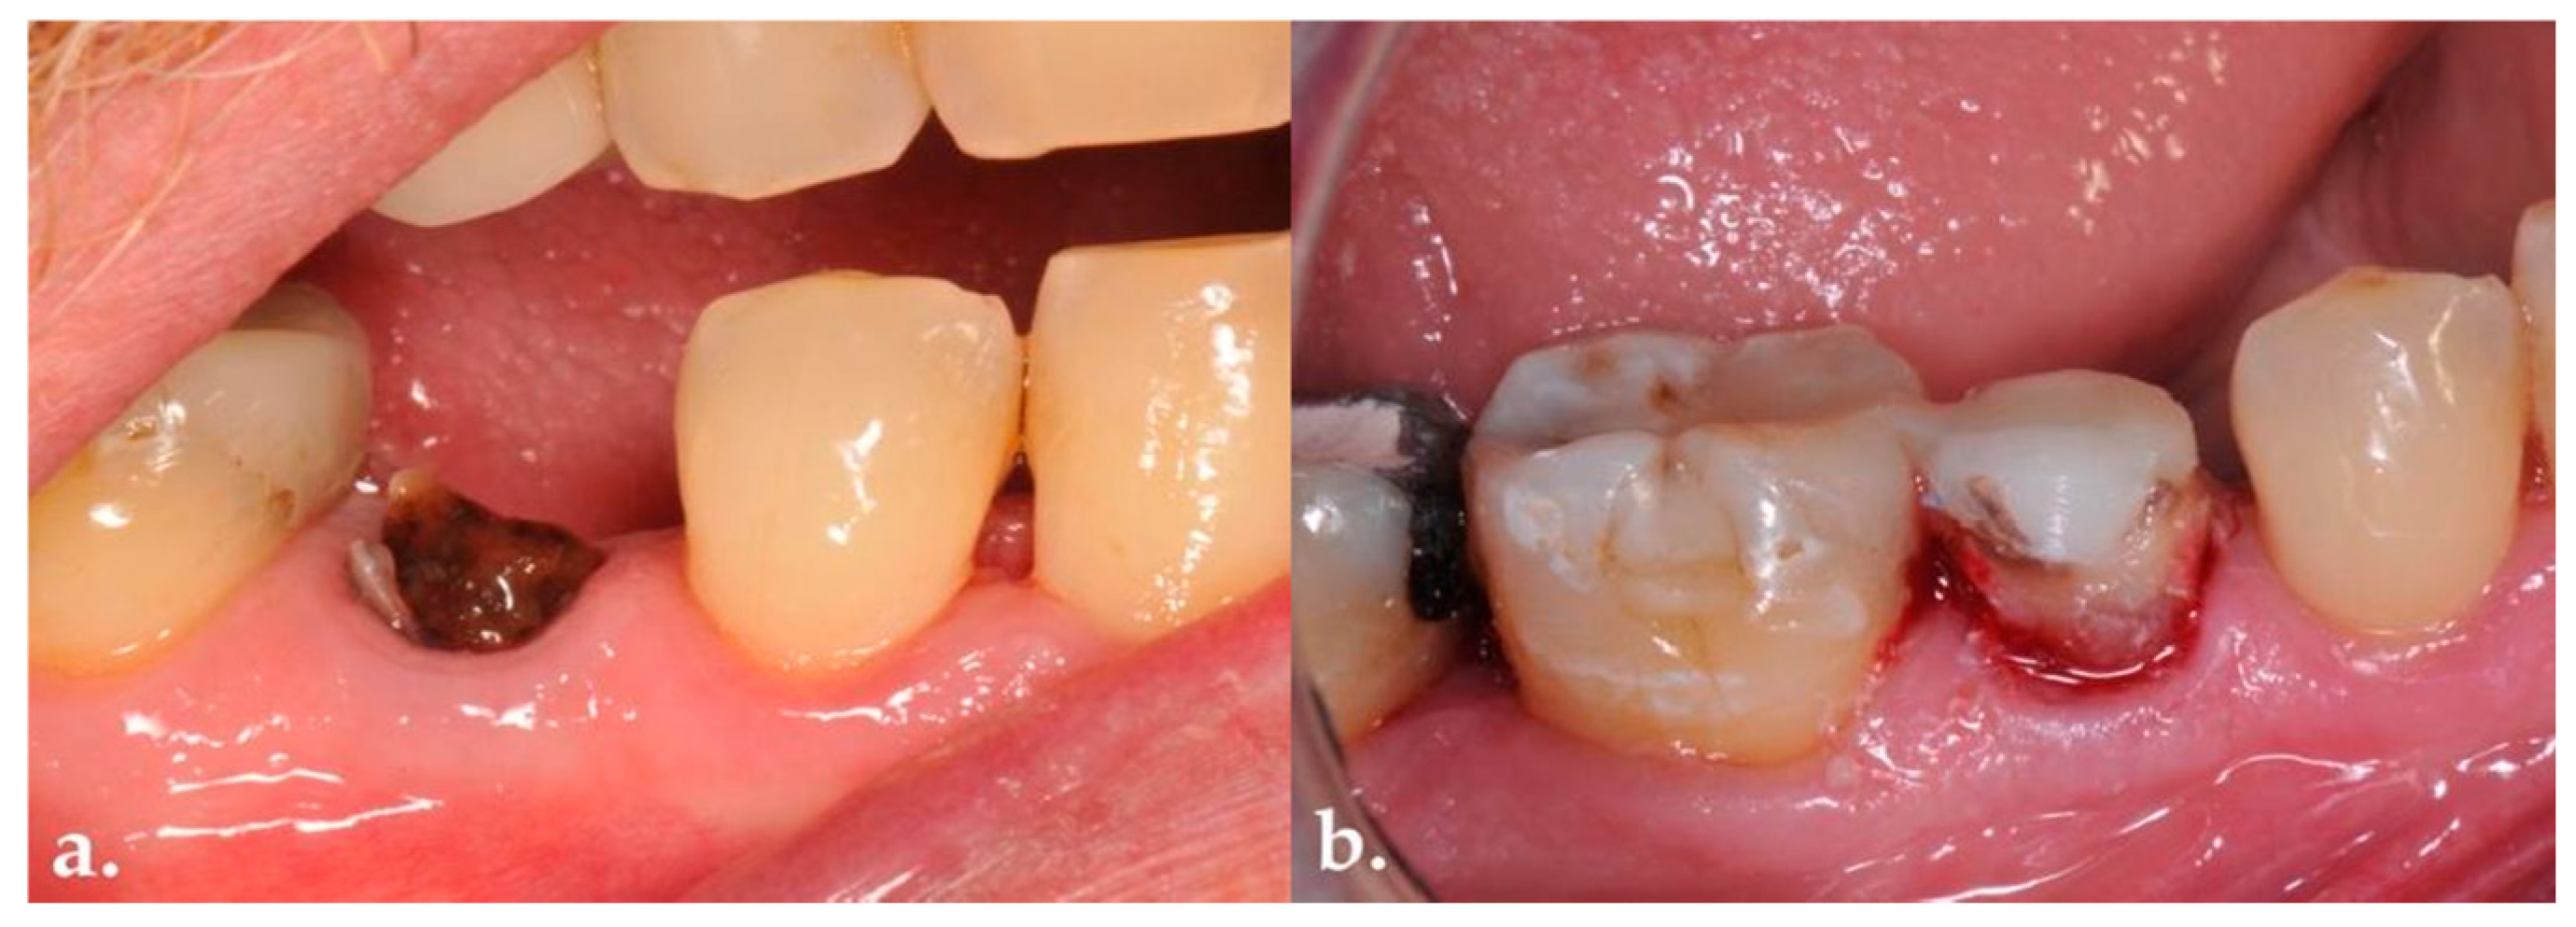

- Presence of a coronal fracture.

- Presence of subgingival carious lesions.